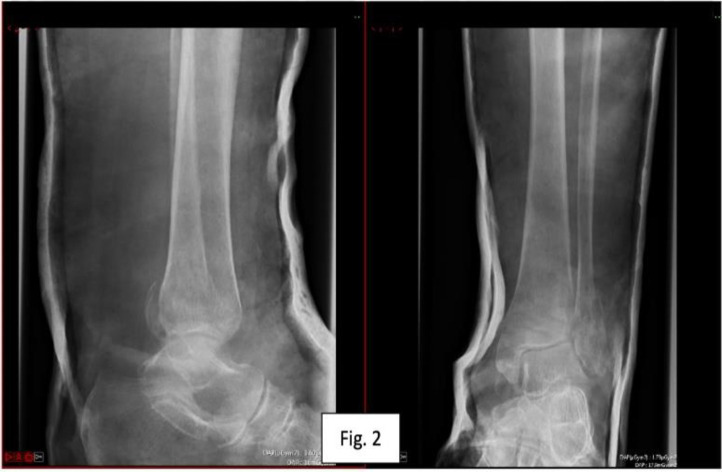

Here we present a novel adaptation of the previously described fibula pro-tibial fixation in a case requiring salvage fixation of a bimalleolar ankle fracture in an osteoporotic patient. Unstable osteoporotic ankle fractures are a challenging injury to manage and typically occur in a frail and comorbid subgroup of patients. Various techniques have been described in the evolution of managing these injuries, e.g. hindfoot nailing and anatomical locking plates, however in this uniquely challenging case a novel strategy was required to mitigate bone loss in the distal fibular fracture fragment. There is some evidence to suggest fibular protibial fixation offers a lower complication profile to its alternatives. The novel use of distal fibula pro-tibial screws offers a new alternative to hindfoot nailing of bimalleolar ankle fracture in osteoporotic bone with compromised distal fibular fragment bone purchase. Further research is required to investigate the compatibility of this technique with early weightbearing.

Abstract Image